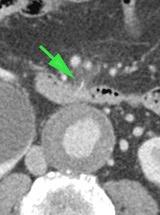

CT tiếp theo xác nhận dày thành ruột non (b.) và thâm nhiễm mỡ (*) trong mạc treo ruột. Ở rãnh cạnh đại tràng trái, phát hiện một xương cá (mũi tên).

Rõ ràng xương cá, sau khi xuyên thủng hỗng tràng, đã di chuyển đến vị trí đó.

Thăm dò nội soi ổ bụng tiếp theo không thể xác định được xương cá.

Bệnh nhân hồi phục tốt với kháng sinh.

CT thực hiện vì lý do khác 18 tháng sau cho thấy xương cá di chuyển nhẹ, rõ ràng đã được bao bọc tốt.

Bệnh nhân vẫn ổn định tám năm sau.